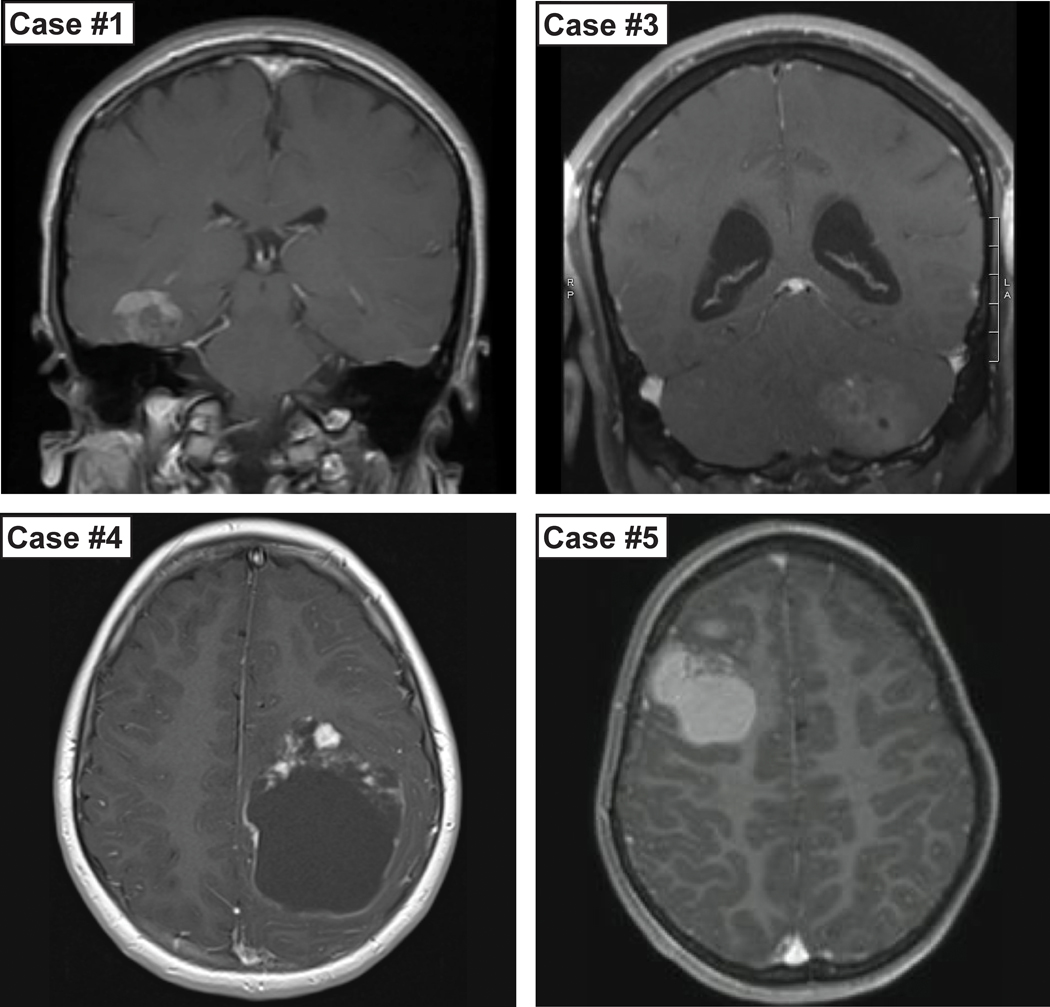

Description:Desmoplastic small round cell tumors (DSRCTs) are highly aggressive sarcomas that most commonly occur intra-abdominally, and are defined by EWSR1-WT1 gene fusion. Intracranial DSRCTs are exceptionally rare with only seven previously reported fusion-positive cases. Herein, we evaluate the clinical, morphologic, immunohistochemical and molecular features of five additional examples. All patients were male (age range 6-25 years; median 11 years), with four tumors located supratentorially and one within the posterior fossa. The histologic features were highly variable including small cell, embryonal, clear cell, rhabdoid, anaplastic and glioma-like appearances. A prominent desmoplastic stroma was seen in only two cases. The mitotic index ranged from <1 to 12/10 HPF (median 5). While all tumors showed strong desmin positivity, epithelial markers such as EMA, CAM 5.2 and other keratins were strongly positive in only one, focally positive in two and negative in two cases. EWSR1-WT1 gene fusion was present in all cases, with accompanying mutations in the TERT promoter or STAG2 gene in individual cases. Given the significant histologic diversity, in the absence of genetic evaluation these cases could easily be misinterpreted as other entities. Desmin immunostaining is a useful initial screening method for consideration of a DSRCT diagnosis, prompting confirmatory molecular testing. Demonstrating the presence of an EWSR1-WT1 fusion provides a definitive diagnosis of DSRCT. Genome-wide methylation profiles of intracranial DSRCTs matched those of extracranial DSRCTs. Thus, despite the occasionally unusual histologic features and immunoprofile, intracranial DSRCTs likely represent a similar, if not the same, entity as their soft tissue counterpart based on the shared fusion and methylation profiles.